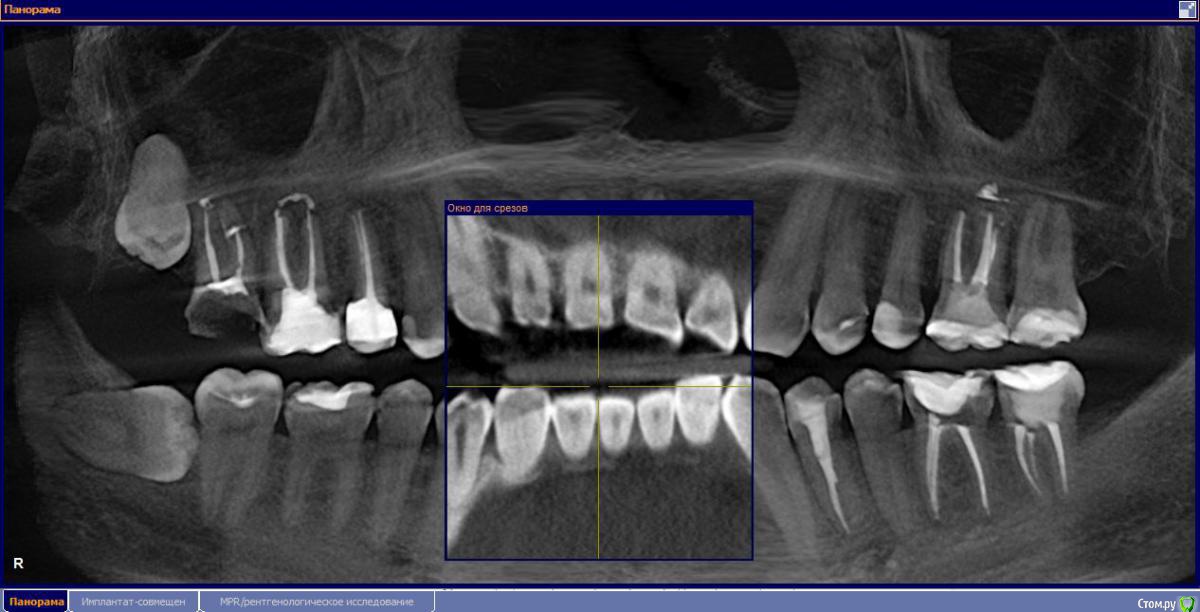

М, 33 года. Есть показания к одновременному удалению 16-го зуба - киста, и 17-го - разрушена верхушка. 8-й предлагают оставить, чтобы "держал кость" (как то так мне озвучили).

- Что по поводу 5го зуба? рекомендуют ставить коронку. и когда это нужно делать, после импантации?

на 15 коронку нужно, да. Когда все остальные коронки будете делать, на имплантатах или зубах.

1.6 большая вероятность сохранить,но понятнее при очном осмотре и диагностическом вскрытии. 1.7,скорее всего,не жилец,но тоже очно взглянуть на него стОит